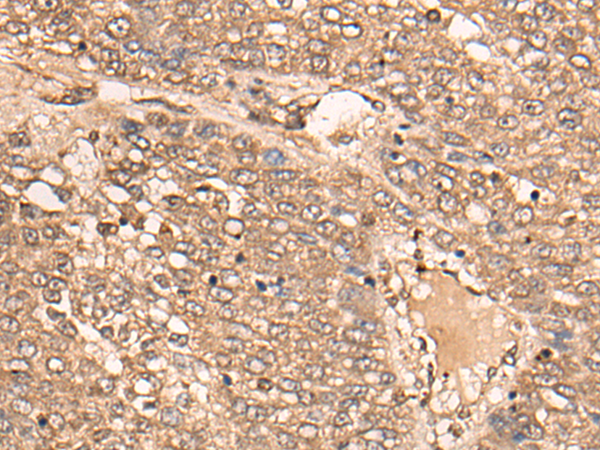

分类: 科研抗体货号: P09304别名: CIR1; UEV1; CROC1; UBE2V; UEV-1; UEV1A; CROC-1应用: WB,IHC反应种属: Human, Mouse